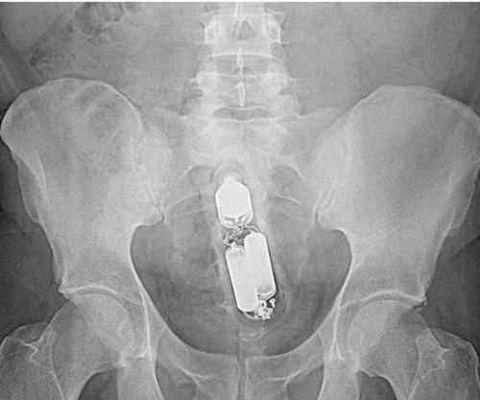

这里面装的*品毒**

手机也可以塞进去